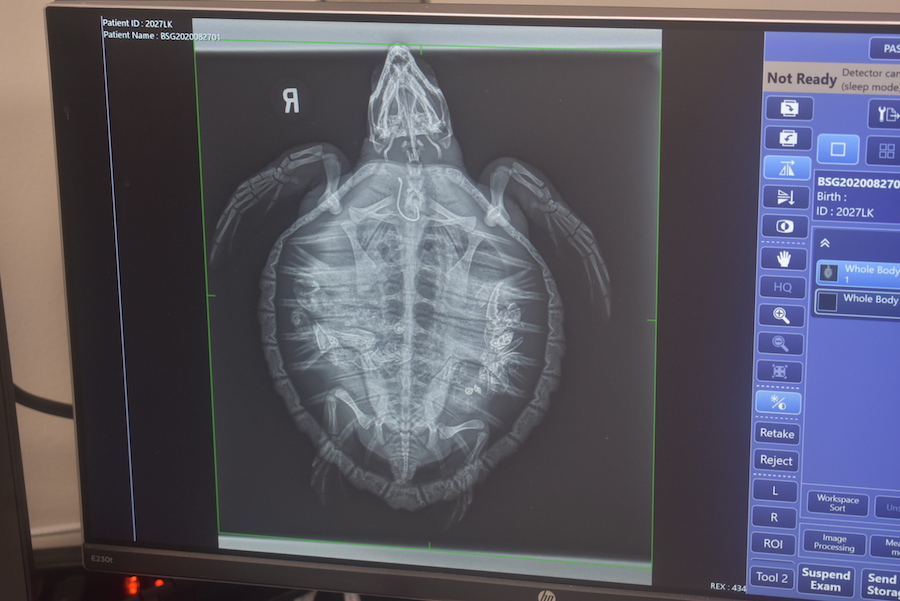

Upon arrival, staff took a radiograph (x-ray) to get an accurate location of the hook. Unfortunately, the line was cut very short, but the x-ray helped staff discern if the hook could be removed via the mouth or if surgery was necessary. Septima was sedated shortly after the radiograph, vitals were monitored, morphometrics were recorded and blood was processed. Once Septima was fully sedated, vet staff and the biologist on call set to work to remove the hook through the mouth. It took quite a while and was not without frustration, but eventually Dr. Boylan was able to successfully remove the hook from her esophagus. Septima’s sedation was reversed, and she spent the night in a bed of foam until she could be placed in a tank for monitoring.